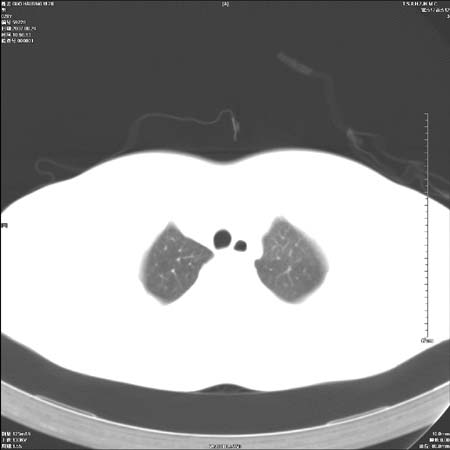

男性,28岁,体检发现左肺病变,患者只有背部隐痛感,哀哉,真不忍心下诊断啊。

左肺门区软组织肿块,左肺上叶支气管开口消失,纵隔内见肿大淋巴结,考虑左中心型肺部,可以做纤支镜取病理确认.

左肺肺门区肿块影,分叶明显,左肺上叶支气管开口受压,纵隔内见肿大淋巴结,考虑左中心型肺癌。